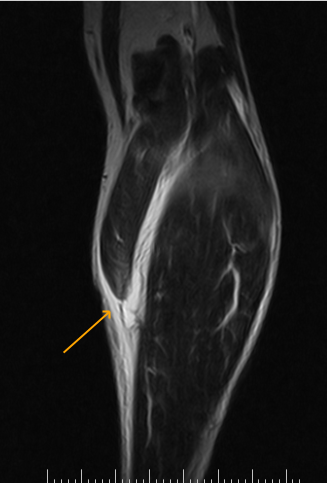

Sintomas e Diagnóstico com MRI

Diagnóstico: físico (defeito, calf-raise). MRI tennis leg diagnóstico edema/retração; ultrassom gradua tear/hematoma, exclui DVT (10%, US Doppler), Aquiles (Thompson). Modern Orthopedics.